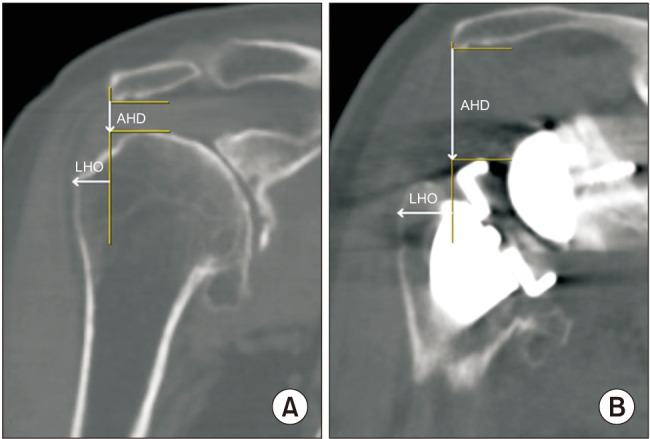

背景:临界肩角(CSA)是一项重要的放射学测量,与三角肌和肩袖生物力学密切相关。我们假设CSA影响逆行全肩关节置换术(RTSA)前后肩关节的生物力学。方法:156例肩胛内侧/肱骨外侧设计行RTSA的患者,根据术前CSA情况分为低CSA组(< 30°)、中CSA组(30°-35°)、高CSA组(> 35°)。通过x线及ct测量三组患者术前、术后肱骨外侧偏移量(LHO)、肩肱距离(AHD)、术后三角肌包裹角(DWA)、三角肌力臂(DMA),并进行比较。比较三组患者在休息和运动时疼痛评分、美国肩关节外科医生评分、加州大学洛杉矶分校肩关节评分和Constant肩关节评分的改善情况。结果:低CSA组术后LHO最大(16.62±4.76 mm),高CSA组术后LHO最小(13.68±5.59 mm, p = 0.03)。术后AHD以低CSA组最高(28.72±5.42 mm),高CSA组最低(25.21±5.12 mm) (p = 0.004)。两组术后DWA、DMA及临床评分改善无显著差异(p < 0.05)。术后发生肩峰骨折5例(3.2%),其中中度CSA组1例,高CSA组4例。结论:低CSA患者肱骨侧化设计的RTSA比中CSA或高CSA患者的肱骨侧化和远端化更多,尽管差异小于5mm。与三角肌活动相关的影像学和术后临床结果的改善,如活动范围、DWA和DMA,在不同csa患者之间没有显著差异。因此,在RTSA期间,CSA对肱骨成分的选择没有帮助,因为基于CSA的临床或功能结果没有显着差异。

Methods: One hundred and fifty-six patients (156 shoulders) who underwent RTSA with medial glenoid/lateral humerus design were divided into 3 groups according to preoperative CSA: low CSA group (< 30°), intermediate CSA group (30°-35°), and high CSA group (> 35°). The preoperative and postoperative lateral humeral offset (LHO) and acromiohumeral distance (AHD) and postoperative deltoid wrapping angle (DWA) and deltoid moment arm (DMA) were measured on x-ray and computed tomography and compared between the 3 groups. The improvement of the pain score, assessed using the visual analog scale at rest and motion, American Shoulder and Elbow Surgeons score, University of California, Los Angeles shoulder score, and Constant shoulder score were compared between the 3 groups.

Results: The postoperative LHO was the highest in the low CSA group (16.62 ± 4.76 mm) and the smallest in the high CSA group (13.68 ± 5.59 mm, p = 0.03). The postoperative AHD was the highest in the low CSA group (28.72 ± 5.42 mm) and the lowest in the high CSA group (25.21 ± 5.12 mm) (p = 0.004). The postoperative DWA, DMA, and improvement of clinical scores were not significantly different between the groups (p > 0.05). Five patients (3.2%) experienced acromion fractures in the postoperative period, including 1 in the intermediate CSA group and 4 in the high CSA group.